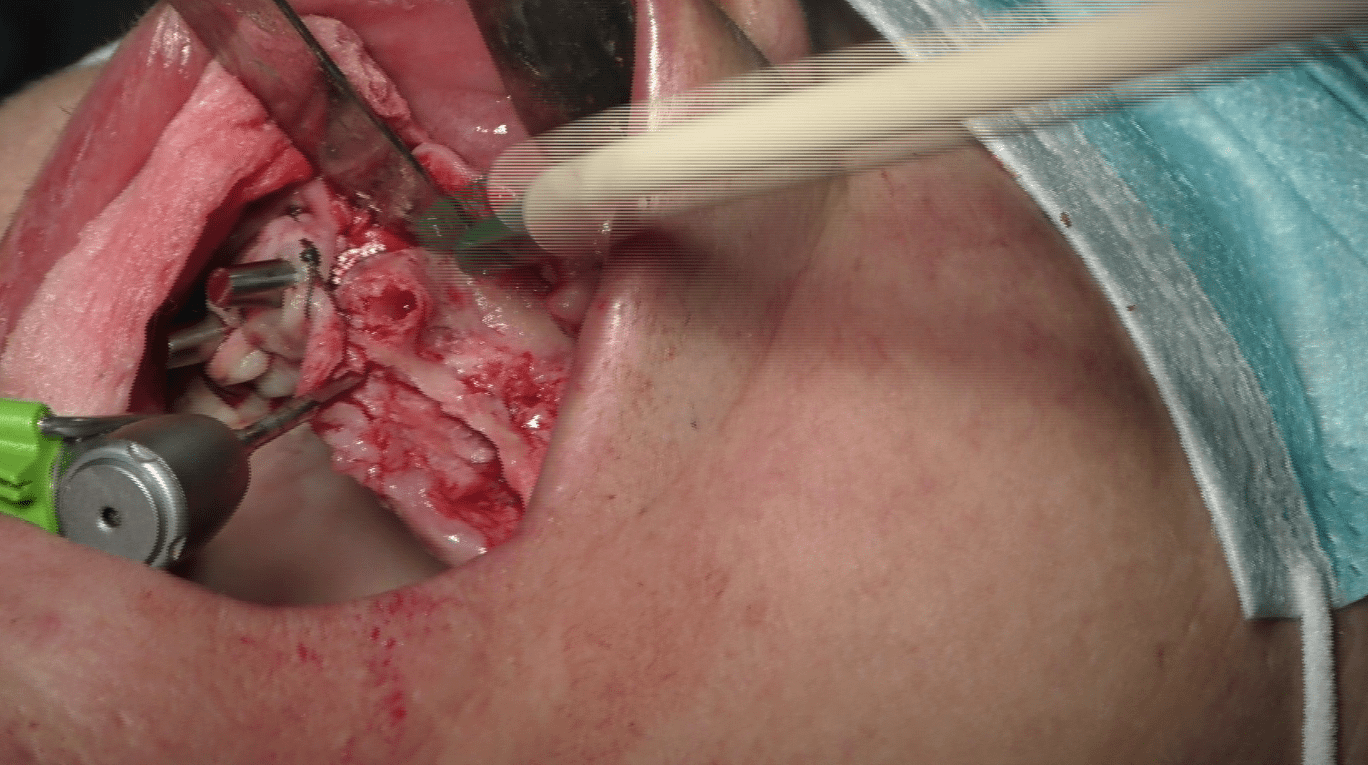

Interventi Preventivi per l’Eccellenza Estetica:

Prima dell’intervento implantare, affrontiamo le atrofie e le zone problematiche attraverso interventi preventivi. Il nostro obiettivo è ottenere non solo una funzione masticatoria ottimale ma anche una soluzione estetica preventivata con il paziente. Garantiamo circolari fissi in ceramica senza falsa gengiva, con elementi dentali che emergono naturalmente senza aggiunte antiestetiche.

Preservazione dei Volumi durante le Estrazioni:

Nelle estrazioni dentali, riempiamo gli alveoli con materiale biocompatibile per preservare i volumi, specialmente nelle zone strategiche per l’estetica vicino al labbro superiore. Questa pratica è fondamentale per ottenere risultati altamente naturali, soprattutto nel contesto estetico femminile.

Una Serie di Piccoli Interventi per un Grande Risultato:

La chiave del nostro successo estetico funzionale è la realizzazione di molteplici piccoli interventi di correzione e mantenimento dei volumi. Ogni dettaglio contribuisce al risultato finale, garantendo un sorriso naturale e duraturo.